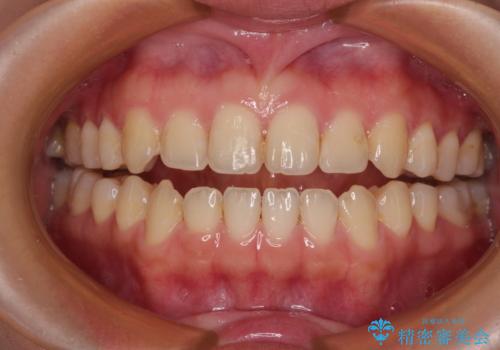

開咬とデコボコを整える インビザライン矯正治療

- 前歯の開咬と叢生を気にして来院された患者様です。

開咬の治療は、前歯を閉じるように動かすとともに、上下臼歯を圧下(骨内にめり込ませる)させることで進めて行きます。

インビザラインは臼歯の圧下を効果的に行えるため、インビザラインを用いて矯正治療を行うこととしました。また、アンカースクリューを用いて、口元の突出感の改善を図りました。

オープンバイトは舌の突出癖により誘発され、治療後も突出癖が残っている容易に後戻りしてしまいます。

治療期間を短縮するためにも、舌突出癖の改善が極めて重要となります。